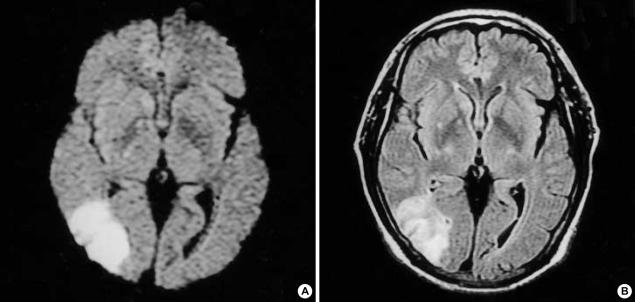

Arterial thrombosis is relatively rare compared with venous thrombosis in nephrotic syndrome. However, the assessment of its pathogenesis and risk factors in individual patient with nephrotic syndrome is necessary to allow appropriate prophylactic management because it is a potentially serious problem. Hereby, with review of the literature, we report a case of a 53 yr-old man with cerebral infarction associated with nephrotic syndrome due to focal segmental glomerulosclerosis during the course of treatments with diuretics and steroid. It reveals that the hypercoagulable state in nephrotic syndrome can be associated with cerebral infarction in adults. Prophylactic anticoagulants can be considered to reduce the risk of serious cerebral infarction in nephrotic patients with risk factors such as severe hypoalbuminemia and on diuretics or steroid treatment, even in young patients regardless of types of underlying glomerular diseases.

与肾病综合征中的静脉血栓形成相比,动脉血栓形成相对少见。然而,对于肾病综合征个体患者的发病机制和危险因素进行评估是必要的,以便进行适当的预防性治疗,因为这是一个潜在的严重问题。在此,通过文献回顾,我们报告一例53岁男性患者,在使用利尿剂和类固醇治疗过程中,因局灶节段性肾小球硬化导致肾病综合征并发脑梗死。这表明肾病综合征中的高凝状态可能与成人脑梗死有关。对于有严重低白蛋白血症等危险因素且正在使用利尿剂或类固醇治疗的肾病患者,即使是年轻患者,无论潜在肾小球疾病的类型如何,都可考虑使用预防性抗凝剂以降低严重脑梗死的风险。